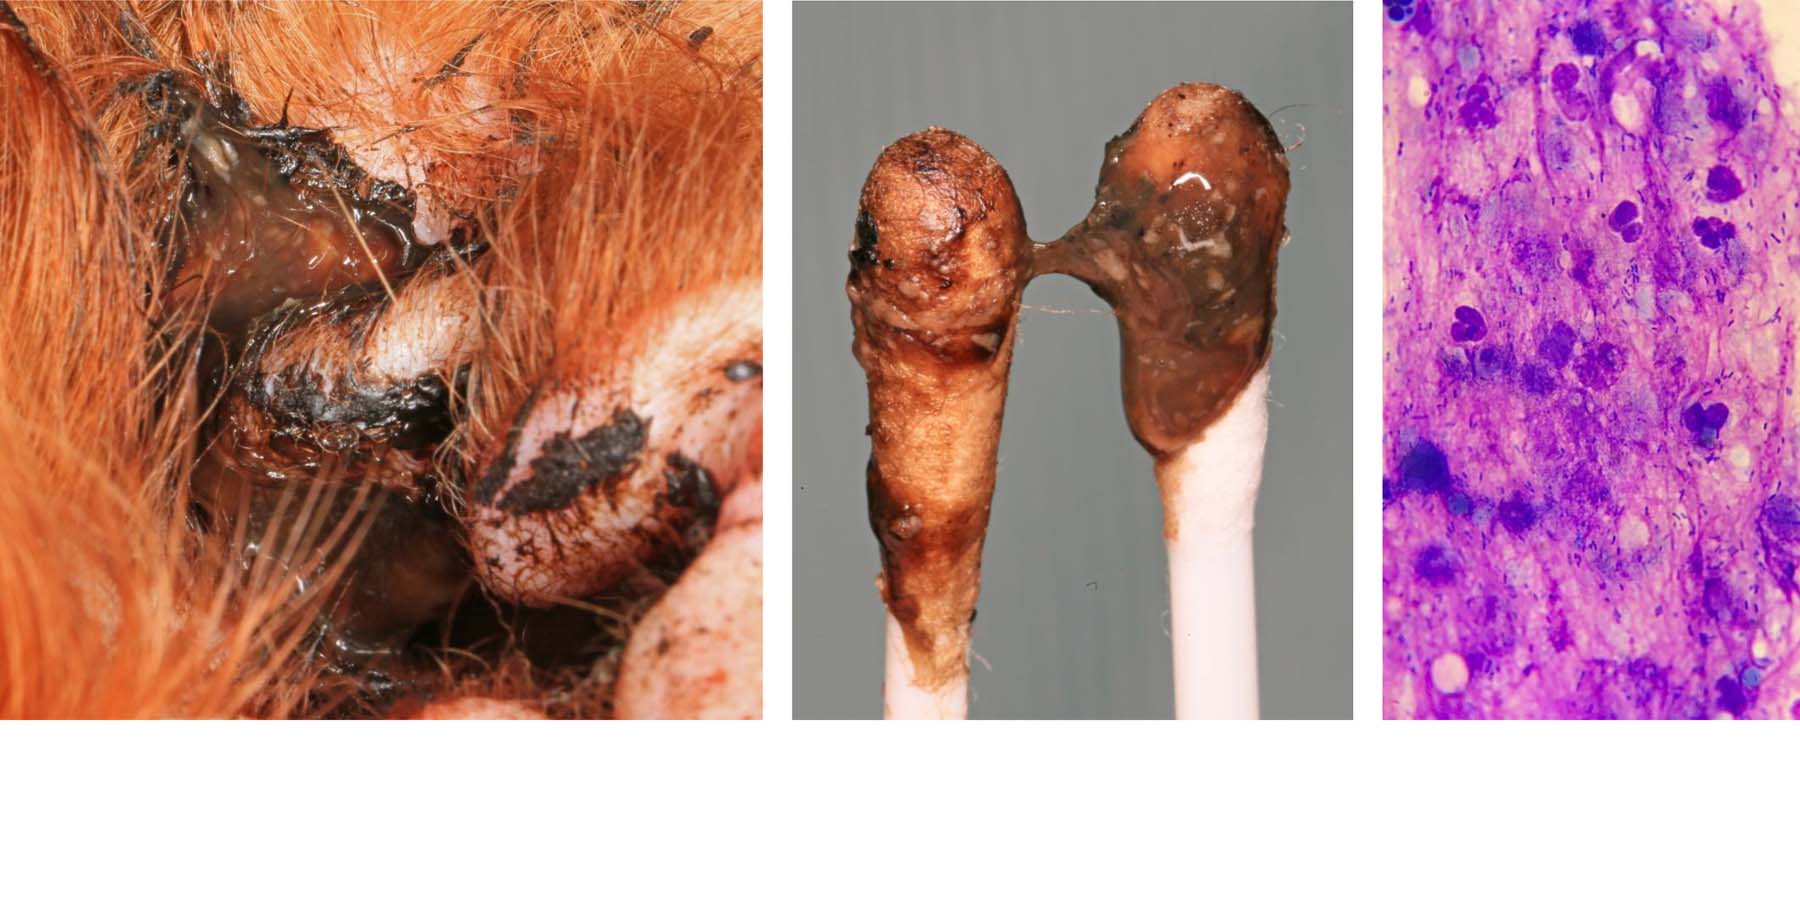

The Challenge of Chronic Otitis in Dogs From Diagnosis to cheap, My Vet Found Rod Bacteria in My Dog s Ears Dog Discoveries cheap, The Challenge of Chronic Otitis in Dogs From Diagnosis to cheap, My Pet Has an Ear Infection Again Village Animal Hospital cheap, Otitis Externa in Animals Ear Disorders MSD Veterinary Manual cheap, The Challenge of Chronic Otitis in Dogs From Diagnosis to cheap, Ear Infections Dr. Christy s Pet Information cheap, Pseudomonas Otitis cheap, The Veterinary Nurse Pseudomonas otitis what nurses need to cheap, My Vet Found Rod Bacteria in My Dog s Ears Dog Discoveries cheap, Ear Infections Mar Vista Animal Medical Center cheap, Otitis Externa in Animals Ear Disorders Merck Veterinary Manual cheap, Ear Cytology Sampling Processing and Microscopic Evaluation cheap, Ear Disease in Canine Patients Today s Veterinary Nurse cheap, The Challenge of Chronic Otitis in Dogs From Diagnosis to cheap, Recurrent or Recalcitrant Ear Infections Otitis Externa The cheap, Ear Infections Gram Negative Otitis In Dogs Veterinary Partner cheap, Ear Infections Mar Vista Animal Medical Center cheap, Dog Ear Infections The Simple and Natural Solution Dogs First cheap, Pilot study of dogs with suppurative and non suppurative cheap, Microorganisms Free Full Text Pseudomonas spp. in Canine cheap, IMG02809.GIF cheap, Ear Disease in Canine Patients Today s Veterinary Nurse cheap, Worst ear infection on a dog. Owner is also a human doctor cheap, Why is your pet licking paws or shaking head Harmony Pet Clinic cheap, Ear Cytology for dogs What is it and why does my vet insist on it cheap, Ear Infections Dr. Christy s Pet Information cheap, Topical Treatment Options for Canine Otitis Externa A Summary for cheap, Ear infections under the microscope Franklin Vets cheap, Ear Swabs Technique Interpretation in Vet Medicine cheap, Recurrent or Recalcitrant Ear Infections Otitis Externa The cheap, Chronic Otitis A Dermatologist s Perspective on Surgery Today s cheap, Pseudomonas ear infection in dogs symptoms and treatment cheap, The pathogenesis of canine otitis externa understanding the cheap, cytology from ears mixed cocci and rod infection Rayya The Vet cheap.

Ear infections under the microscope Franklin Vets

Ear Swabs Technique Interpretation in Vet Medicine

Chronic Otitis A Dermatologist s Perspective on Surgery Today s